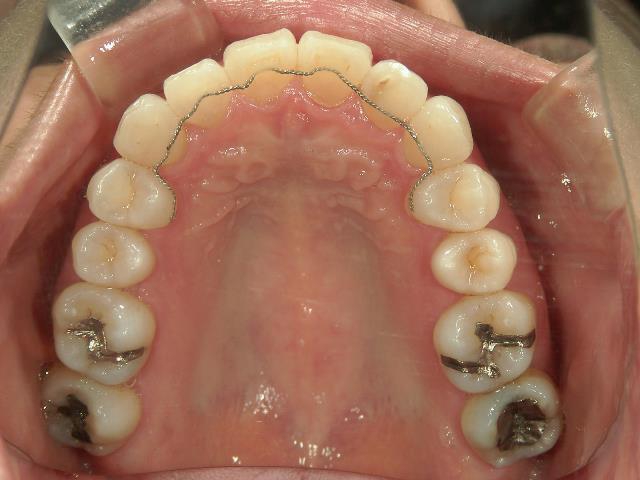

矯正歯科 治療後 ミニインプラントを2本埋入し、下顎前歯を圧下

矯正_灰色.pngno.41_8994_治療後_上.JPG矯正_灰色.png